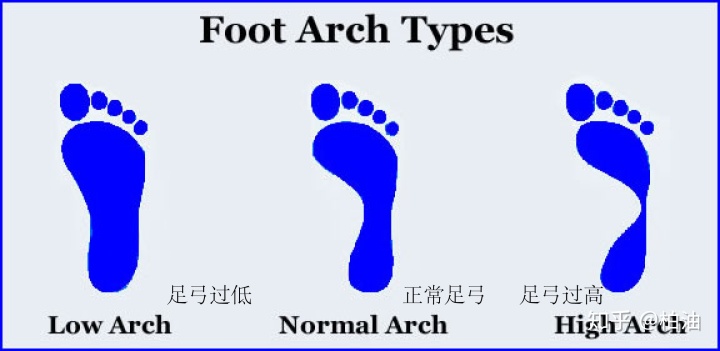

除了扁平足之外,足弓还有可能因为各种原因变得过高,足弓也是一种异常现象,会影响足弓的正常功能。所以在我们对足弓进行训练和改善之前,我们首先要明确自己的足弓类型。

一般来说,足弓有三种,即正常足弓、高足弓和平足弓,判断的方法很简单。

准备一块干净的厚纸板,将脚底在水中浸湿,踩到厚纸板上,根据脚印形状来判断足弓类型。

- 正常足弓

脚印的最窄处约为最宽处的1/3,说明足弓是正常的。

- 足弓过高

脚印的最窄处明显少于最宽处的1/3,说明足弓过高。

- 足弓过低

脚印的最窄处明显多于最宽处的1/3,说明足弓过低,是扁平足。严重的扁平足,脚印的中间区域甚至会比前脚掌更宽。

需要再强调一点,足弓的类型既有结构性的(包括先天和后天的结构异常),也有功能性的(主要是肌肉和软组织失衡)。判断的方法是根据自然状态和承重状态下足弓形状是否发生变化来判断。

比如,有扁平足问题的小伙伴在做上述测试时,测两次,一次是全力踩上去,一次是轻轻地放上去,然后比较两次脚印。如果一样,那么说明是结构性的扁平足,如果不同,那么很可能是功能性的原因造成的,可以通过运动进行调整。